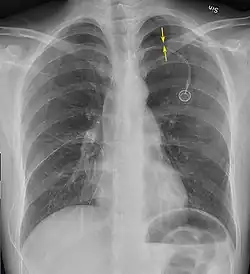

Chest X-ray

A plain chest radiograph, ideally with the X-ray beams being projected from the back (posteroanterior, or "PA"), and during maximal inspiration (holding one's breath), is the most appropriate first investigation.[35] It is not believed that routinely taking images during expiration would confer any benefit.[36] Still, they may be useful in the detection of a pneumothorax when clinical suspicion is high but yet an inspiratory radiograph appears normal.[37] Also, if the PA X-ray does not show a pneumothorax but there is a strong suspicion of one, lateral X-rays (with beams projecting from the side) may be performed, but this is not routine practice.[18][22]

Anteroposterior expired X-ray at the same time, more clearly showing the pneumothorax in this case -

Chest X-ray showing a pneumothorax on the right (left in the image), where the absence of lung markings indicates that there is free air inside the chest -

It is not unusual for the mediastinum (the structure between the lungs that contains the heart, great blood vessels, and large airways) to be shifted away from the affected lung due to the pressure differences. This is not equivalent to a tension pneumothorax, which is determined mainly by the constellation of symptoms, hypoxia, and shock.[16]

The size of the pneumothorax (i.e. the volume of air in the pleural space) can be determined with a reasonable degree of accuracy by measuring the distance between the chest wall and the lung. This is relevant to treatment, as smaller pneumothoraces may be managed differently. An air rim of 2 cm means that the pneumothorax occupies about 50% of the hemithorax.[18] British professional guidelines have traditionally stated that the measurement should be performed at the level of the hilum (where blood vessels and airways enter the lung) with 2 cm as the cutoff,[18] while American guidelines state that the measurement should be done at the apex (top) of the lung with 3 cm differentiating between a "small" and a "large" pneumothorax.[38] The latter method may overestimate the size of a pneumothorax if it is located mainly at the apex, which is a common occurrence.[18] The various methods correlate poorly but are the best easily available ways of estimating pneumothorax size.[18][22] CT scanning (see below) can provide a more accurate determination of the size of the pneumothorax, but its routine use in this setting is not recommended.[38]

Not all pneumothoraces are uniform; some only form a pocket of air in a particular place in the chest.[18] Small amounts of fluid may be noted on the chest X-ray (hydropneumothorax); this may be blood (hemopneumothorax).[16] In some cases, the only significant abnormality may be the "deep sulcus sign", in which the normally small space between the chest wall and the diaphragm appears enlarged due to the abnormal presence of fluid.[19]